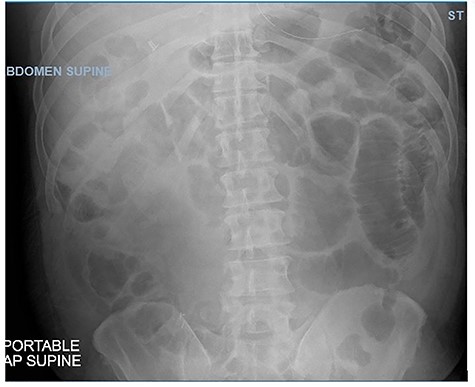

Postoperatively, the patient remained NPO with an NG tube for 8 days. On Day 9, his abdominal X-ray (Fig. 2) was much improved and without air-fluid levels, he was passing flatus, and his abdominal exam was clinically benign. He was started on a clear liquid diet and advanced to a regular diet over the next day. The patient was discharged 13 days after the admission. He was tolerating his diet and had regular bowel function with no further symptoms of abdominal pain, nausea or vomiting.

Abdominal X-ray showing dilated loops of bowel on Day 9 of admission.